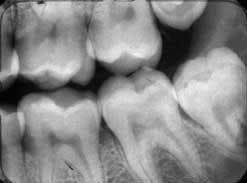

• For the bicuspid view, the film is placed in the arch with the mesial of the film just barely touching the distal of the cuspid, if present. The bicuspid view will incorporate a full view of the first molar region as well. On the upper jaw, the angle of the X-ray head is preset at 30 to 35 degrees and the face of the tube parallel to the bicuspid-first molar region. Once the film is placed as described, aim the face of the tube like a rifle so the beam will be passing through the face of the teeth being X-rayed, without overlapping of the interproximal and avoiding cone cutting. Actually, you should determine that the open face of the tube is parallel to the bicuspid and first molar, and that the entire film is within the parameters of the open tube. With practice, this procedure should not take more than five to 10 seconds.

• Properly imaging the molar view in the arch depends on placing the film opposite the third molar area. This is done in a similar way as is used for the bicuspid view, except that the mesial of the film as it is placed in the mouth must be at the middle of the first molar. The patient is biting lightly on the Styrofoam holder. The angle of the X-ray head is set at 20 to 25 degrees in the upper arch. Once again, it's important to develop the ability to bring the face of the tube parallel to the second and third molars and aim the tube to send the beams perpendicular to the film to avoid overlapping. If the film is viewed as being entirely within the face of the tube, you will avoid cone cutting and interproximal distortion. This gives you a clear view of the second and third molar area, the distal half of the first molar and surrounding bone and soft tissue.

The most common errors seen are the overlapping of bicuspids on the cuspid view. This occurs because the film has not been placed with the cuspid in the middle of the film, and the head of the X-ray is turned so that the beam is casting the shadow from the distal through the bicuspids onto the cuspid, or because the beam is casting the shadow from the mesial through the cuspid overlapping on the bicuspids. Remember, you are aiming the beam like a rifle, and the beam is a bullet that must pass through the face of the tooth or teeth you want to X-ray. The open face of the tube must be parallel to the face(s) of the teeth being X-rayed.